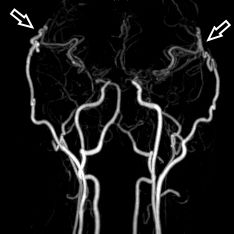

3D MRT Darstellung

1 Jahr postoperativ: 3D MRT Darstellung der extrakraniellen-intrakraniellen Bypässe (Pfeile)